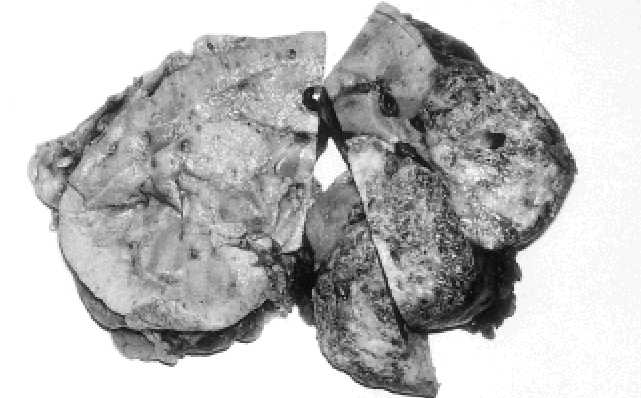

Poměr žen a mužů s angiomyolipomem postižených tuberózní sklerózou i bez tuberózní  sklerózy  je  přibližně  4,5:1(127).  Růst  angiomyolipomů  je  pravděpodobně ovlivněn  hormonálně,  což  lze  soudit  z  jejich  zrychleného  růstu  během  těhoten- ství(145). Průměrný věk pacientů v době diagnózy bývá 35 let pro pacienty s tuberóz- ní sklerózou a 45-55 let pro pacienty bez ní. U dětí s tuberózní sklerózou je možné angiomyolipom vidět běžně, ale u dětí bez tuberózní sklerózy je vzácn . Byl popsán i  kongenitální  případ  angiomyolipomu(390).  Většina  angiomyolipomů  menších  než 4 cm je asymptomatická, ale větší angiomyolipomy se běžně prezentují bolestí v bo- ku, hematurií, palpační rezistencí v břiše a někdy i nevysvětlitelnou hypertenzí a ho- rečkami(127). Počítačovou tomografií a  ultrasonograficky je možné rozpoznat angio- myolipom  podle  denzity  tukové  tkáně  obsažené  v  nádoru(89).  Ty  angiomyolipomy, které sestávají převážně z  hladké svaloviny, mohou být nerozpoznatelné od renál- ních karcinomů. Typický angiomyolipom se chová benigně. V literatuře je popsáno asi 20 případů extenze angiomyolipomů do dolní vena cava a  vzácně až do pravé síně srdeční(215). Asi 40 případů angiomyolipomů mělo též ložika nádorů v přilehlých uzlinách. Tato ložiska angiomyolipomů nelze považovat za metastázy, ale za multi- fokální  ložiska  angiomyolipomů,  která  se  i   v   uzlinách  chovají  zcela  benigně. přestože se angiomyolipomy chovají benigně, komplikace, které způsobují, mohou být  nebezpečné.  Přítomnost  velkého  množství  cév,  které  nemají  elastickou  vrstvu v angiomyolipomech, je příčinou častých krvácení do retroperitonea. Toto krvácení angiomyolipomů  do  retroperitonea  se  též  nazývá  Wunderlichův  syndrom(80).  Další komplikací  angiomyolipomu  je  renální  selhání,  které  vzniká  asi  u  15  %  pacientů s tuberózní sklerózou. Vzácně angiomyolipom vykazuje rozsáhlou extenzi do peri- renálních struktur, která může působit vážné potíže. Farrow a  spol. zmínili 2 paci- enty  s  inoperabilními  angiomyolipomy,  které  masivně  extendovaly  do  okolních 99 F. MEZENCHYMOVÉ NÁDORY LEDVINY F.1. ANGIOMYOLIPOM A KOMPLEX TUBERÓZNÍ SKLERÓZY I když je angiomyolipom nejčastější mezenchymální tumor ledviny, jeho zvláštní histologické složení způsobuje mnohdy vážné diagnostické potíže. Poprvé byl ter- mín angiomyolipom použit Grawitzem již v roce 1900(177). Až do nedávna se angio- myolipom považoval za hamartom, ale Green v roce 1996 prokázal klonální původ angiomyolipomu(179). autoři z Verony navrhli původ angiomyolipomu v perivaskulár- ních epiteloidních buňkách. Podle nich se perivaskulární epiteloidní buňky mohou diferencovat jednak do vřetenat ch buněk majících rysy hladké svaloviny, do tuko- vých buněk a do eozinofilních nebo světlých buněk. Perivaskulární epiteloidní buň- ky mohou kromě angiomyolipomu dávat vznik i jiným tumorům extrarenálních or- gánů, jako například lymfangiomatóze a světlobuněčnému "cukrovému" tumoru plic a pankreatu(51,520) a též tzv. PEComům, což jsou intraabdominální maligní tumory bez vztahu k  ledvinám, ale sestávající z  identických perivaskulárních epiteloidních bu- něk(50). Chowdhury a  spol. studovali archivní materiál z  ledvin od pacientů s  tube- rózní sklerózou a u 3 těchto pacientů našli celkem 72 drobných uzlů, které předsta- vovaly angiomyolipomy ve zcela počátečním stadiu vývoje(84). Fujii a spol. zjistili, že ve vzorku neselektované populace 18000 asymptomatických dospělých lidí jsou an- giomyolipomy dokonce ještě častější než renální karcinomy(157). Ve skupině 95 paci- entů s tuberózní sklerózou z Mayo Kliniky Stilwell a spol. zjistili, že 47 % pacientů s   tuberózní  sklerózou  mělo  angiomyolipomy,  z   nichž  71  %  bylo  bilaterálních a  87 % angiomyolipomů bylo mnohotných(453). Stejně tak Cook a  spol. našli angio- myolipomy ledvin u 49 % ze 139 pacientů s tuberózní sklerózou(95). Dle Gomeze se přítomnost  tuberózní  sklerózy  rozpozná  podle  několika  jednotlivých  znaků  nebo podle kombinace znaků, které jsou uvedeny v Tabulce(173). Tabulka Přítomnost jakéhokoliv z následujících znaků je diagnostická: - Mnohočetné renální angiomyolipomy - Tuber v cerebrálním kortexu - Gliální uzly v subependymu - Retinální hamartomy - Faciální angiofibromy - Unguální fibromy - Fibrózní plaky ve vlasaté části hlavy nebo na čele Přítomnost jakéhokoliv z následujících znaků je podezřelá z tuberózní sklerózy a přítomnost dvou znaků je určující: - Mnohotné renální tumory nebo cysty - Plicní lymfangiomyomatóza - Kardiální rabdomyom - Příbuzný v rodině s tuberózní sklerózou - CNS: infantilní spasmy, kalcifikace nebo hypomyelinizace - Kůže: hypomelanotické makuly, šagrénové skvrny 98 KRITÉRIA PRO DIAGNÓZU TUBERÓZNÍ SKLERÓZY(173) Obr. F.1.1. Angiomyolipomy jsou typicky žluté až růžově zbarvené, místy tmavě červené, což závisí na poměrném zastoupení tukové tkáně, hladké svaloviny a ložisek krvácení.